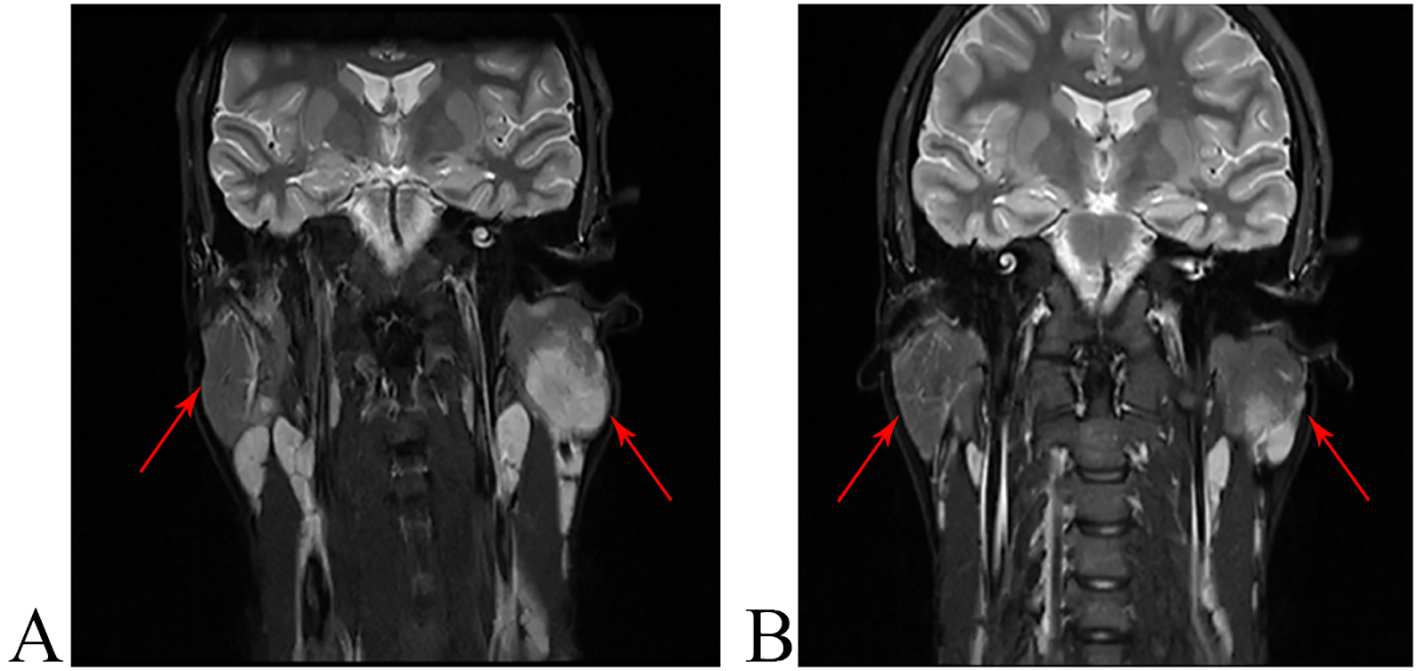

MRI scans in coronal view showing bilateral parapharyngeal masses (red arrows). Image A was taken before treatment, and image B at week 20 of treatment.

Figure 2. Radiological appearance of KD lesions on short-tau inversion-recovery T2-weighted fast spin-echo images. (A) The MRI results before treatment with dupilumab showed multiple space-occupying lesions in both parotid glands, with the largest measuring 2.8×2.3×3.5cm. (B) At week 20 of treatment, the MRI still showed multiple space-occupying lesions in both parotid glands, but the largest one measured only 1.8 × 0.6 × 2.4 cm.

A 19-year-old male complained of masses behind both ears for two months. Intravenous cefuroxime and ribavirin were administered for two weeks at a local hospital, however, the masses gradually increased in size. A biopsy was conducted, and the result indicated eosinophilic lymphatic granuloma. Subsequently, he was admitted to our hospital. Admission blood tests indicated the following: white blood cell (WBC) count 11.2×103/µL (normal 3.5 - 9.5×103/µL), EO count 3.57×103/µL (normal 0.02 - 0.52×103/µL), IgE 1080IU/ml (normal < 100 IU/ml). The results for hepatic, renal functions, and urinalysis were within normal limits. The bone marrow biopsy suggested eosinophilia. Ultrasound revealed enlarged lymph nodes in the neck, parotid glands, and supraclavicular region. According to the clinical and histopathological findings, a diagnosis of Kimura’s disease was made. Oral methyl-prednisolone (32mg/d) was administered. Two weeks after the treatment, the cervical, supraclavicular, and parotid lymph nodes regressed, the size of the masses slightly decreased, the absolute EO count reduced to 1.74×103/µL, but the IgE level rose to 1550 IU/ml. The methyl-prednisolone dose was reduced to 16mg, and mycophenolate mofetil (1.0g/d) was added. This treatment lasted for four months, however, there was no significant change in the masses. Due to personal reasons, medication was discontinued, and the masses began to enlarge again. Upon his return to our department, he had been off medication for 10 months. The size of the masses was larger than when he first visited our department (Figures 1A–C). Laboratory results indicated a WBC count of 14.3×103/µL, an EO count of 7.06×103/µL, and an IgE level of 4810 IU/ml. The MRI results indicate multiple space-occupying lesions in both parotid glands, with the largest measuring 2.8×2.3×3.5cm (Figure 2A). Treatment with dupilumab was initiated at 600mg, followed by 300mg every two weeks. At the 16-week follow-up, blood tests revealed a WBC count of 10.7×103/µL, an EO count of 1.41×103/µL, and an IgE level of 1180 IU/ml. At week 20 of treatment, we performed a follow-up MRI, which still showed multiple space-occupying lesions in both parotid glands, but the largest one measured only 1.8×0.6×2.4cm (Figure 2B). Subsequently, the treatment was adjusted to 300mg every four weeks for a duration of 32 weeks (Figures 1E–G). Now the treatment has been adjusted to 300mg every six weeks, and the condition has been well controlled.